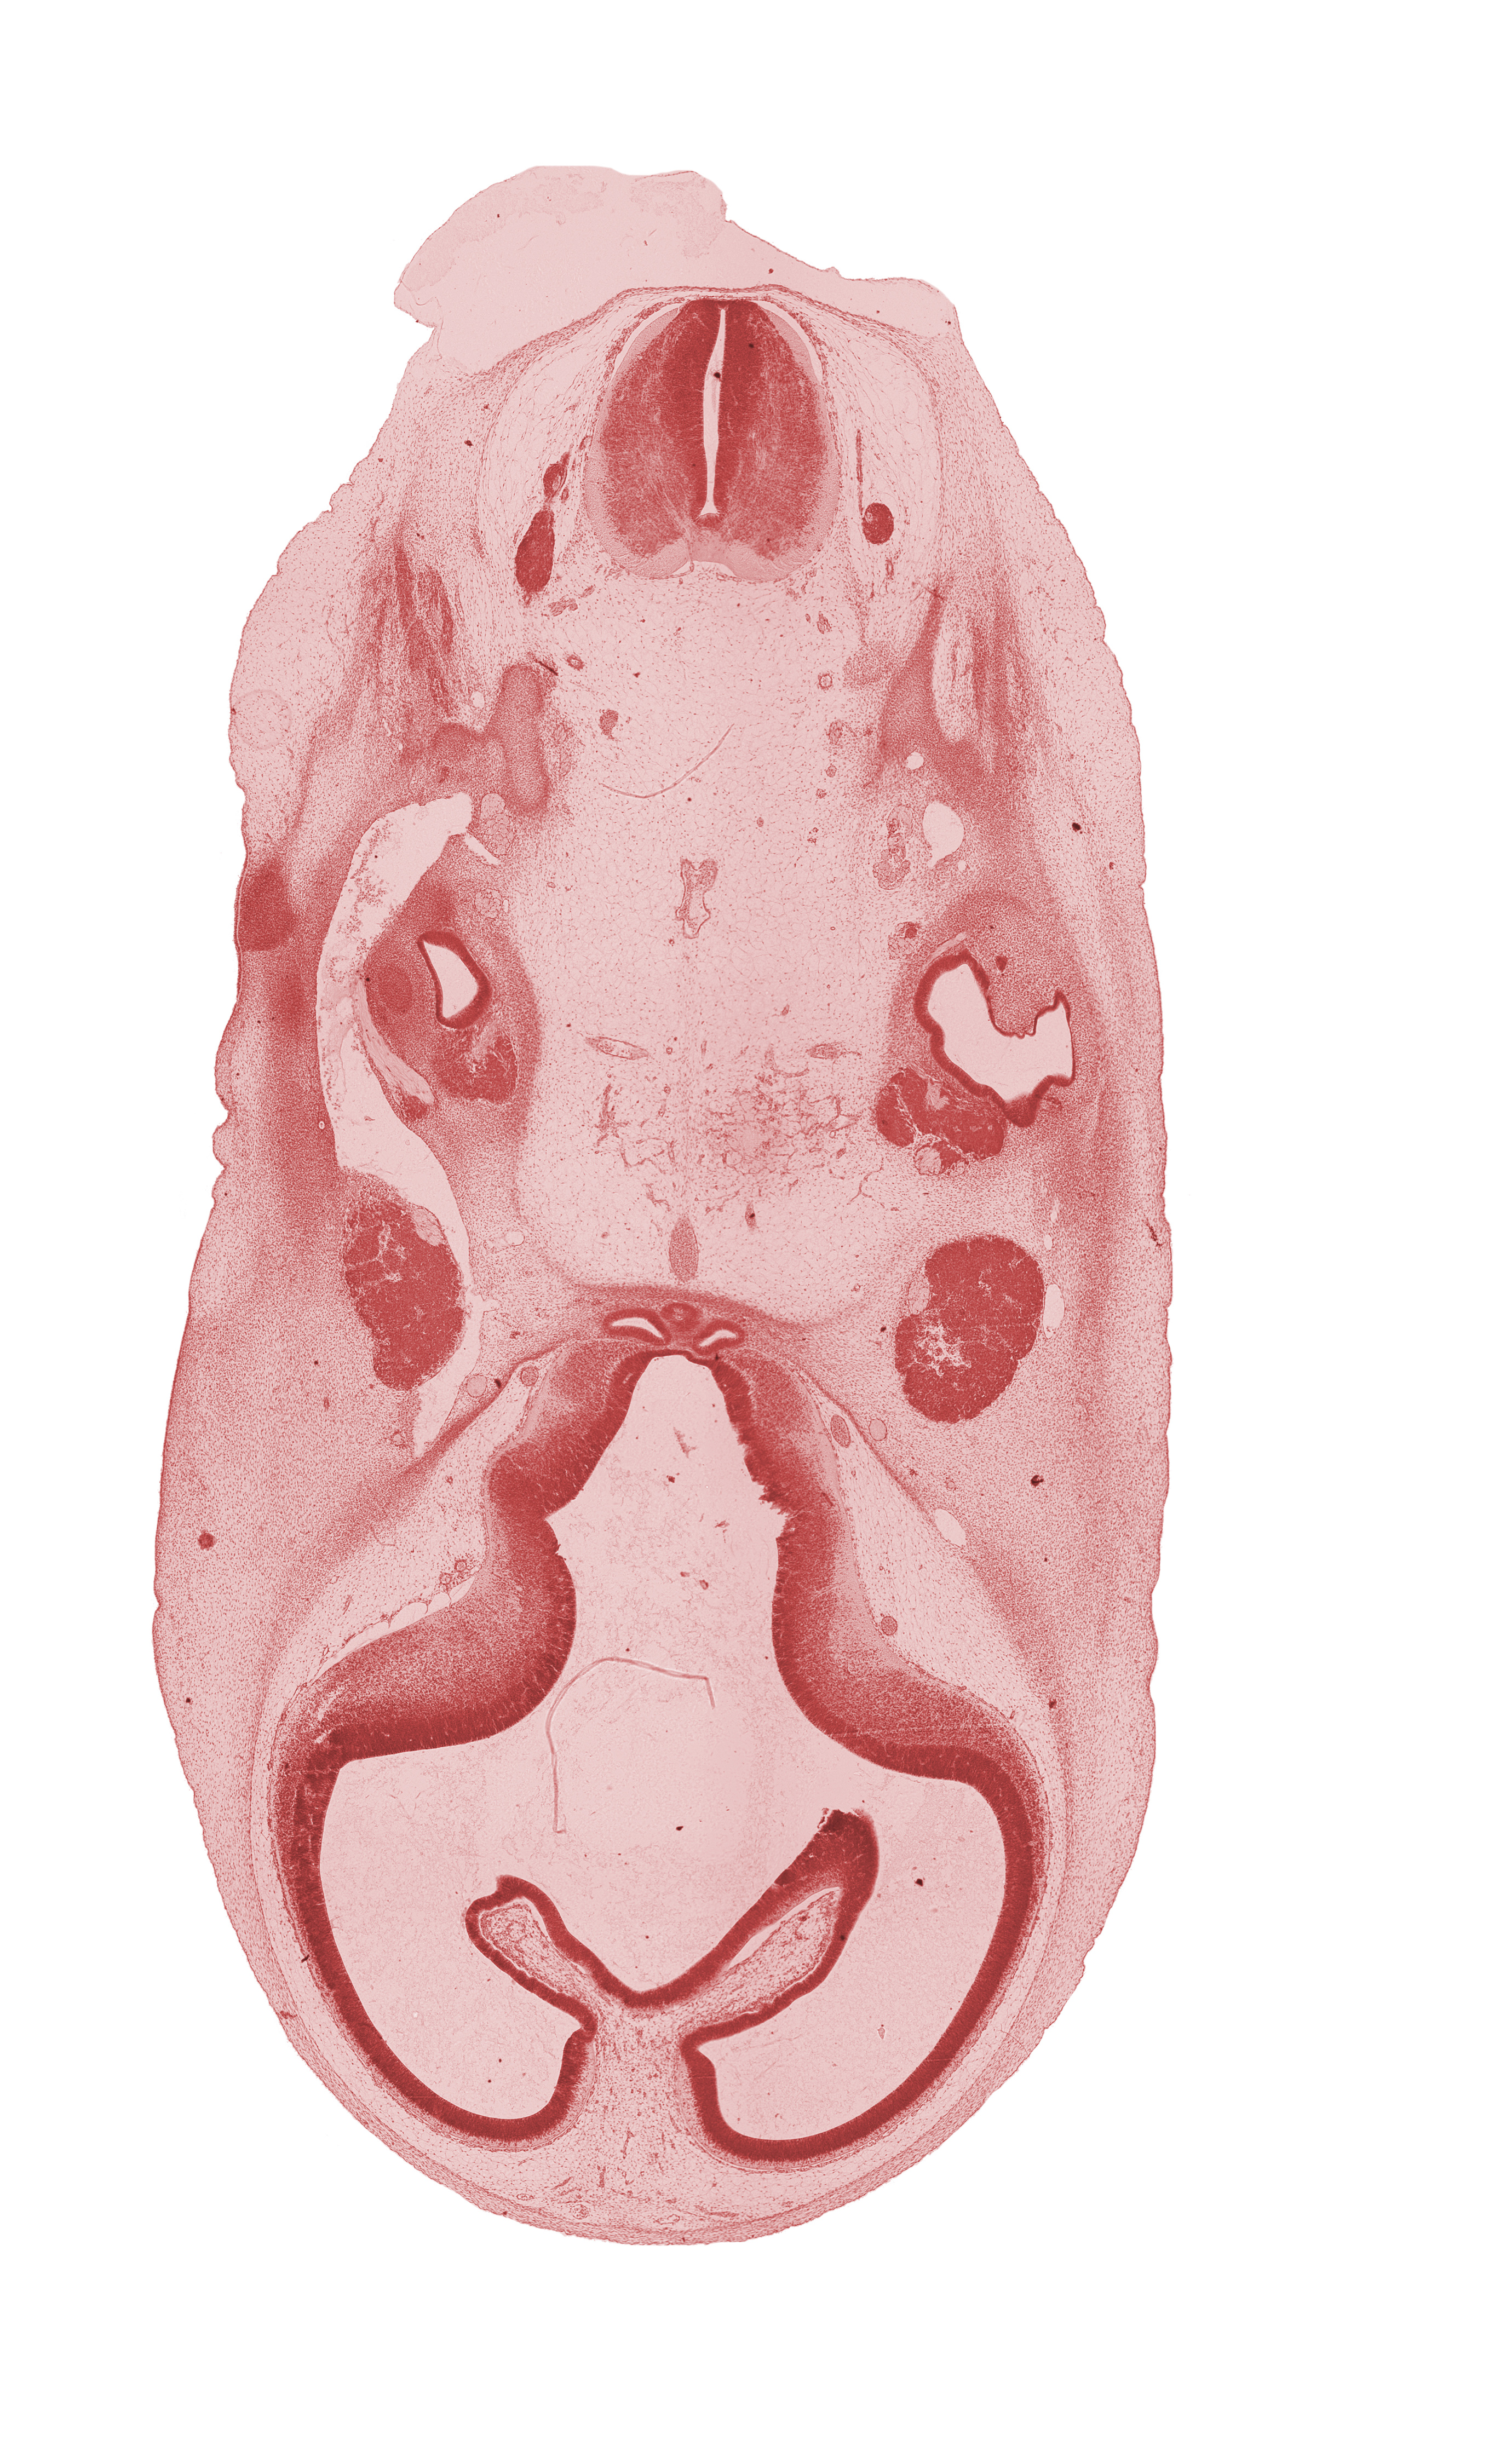

Carnegie Embryo #4430 | Location: 10-19

Keywords: accessory nerve (CN XI), basilar artery, choroid fissure, corpus striatum, edge of pons region (metencephalon), hippocampal thickening, lateral semicircular duct, motor root of trigeminal nerve (CN V), neurohypophyseal bud, primary head vein, spinal accessory nerve (CN XI), subarachnoid space, torus hemisphericus, trigeminal ganglion (CN V), tuberal part of adenohypophysis, vagus nerve (CN X), vertebral artery, vestibular part of otic vesicle

Source: The Virtual Human Embryo.